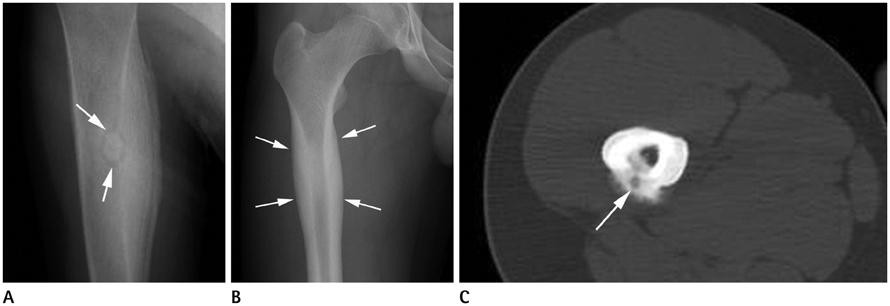

Systematic Approach of Sclerotic Bone Lesions Basis on Imaging Findings

- Sclerotic bone lesions are common, but there are diverse groups of tumors and non-tumorous lesions. Although plain radiograph and computed tomography can reveal important characteristics of these lesions, diagnosis is often challenging for radiologists. A systematic approach and familiarity with the imaging features of various sclerotic bone lesions may be greatly helpful for eliminating in the differential diagnosis. This review describes the systematic approach to diagnosing sclerotic bone lesions based on imaging findings.